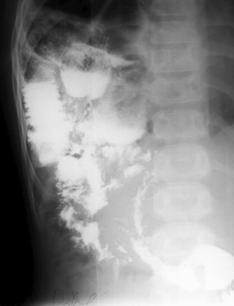

Fig. 26: Hernie traumatica de intestin subtire si colon prin ruptura de diafragm (opacitate intensa, neomogena, pe fondul careia apar o serie de transparente cu aspect de arcuri de cerc situata in baza dreapta: tranzitul baritat confirma diagnosticul)

Fig. 27 – Hernie hiatala prin alunecare

Herniile diafragmatice

A)      Herniile prin hiatusul esofagian – sunt descrise trei tipuri de hernie dupa clasificarea lui Ackerlund:

hernii prin brahiesofag (congenital sau secundar unei esofagite peptice): cardia este situata intratoracic, esofagul este scurt, implantat in capul pungii herniate;

hernii paraesofagiene: cardia este in abdomen, iar fornixul gastric este herniat transhiatal, de-a lungul marginii stangi a esofagului;

hernii prin alunecare: fornixul, cardia si esofagul abdominal se afla situate intratoracic. Esofagul are lungime normala.